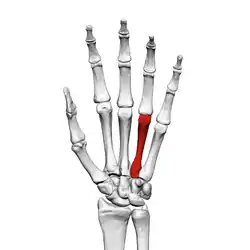

Fourth metacarpal of the left hand (shown in red). Palmar view.

The fourth metacarpal bone (metacarpal bone of the ring finger) is shorter and smaller than the third.

The base is small and quadrilateral; its superior surface presents two facets, a large one medially for articulation with the hamate, and a small one laterally for the capitate.

On the radial side are two oval facets, for articulation with the third metacarpal; and on the ulnar side a single concave facet, for the fifth metacarpal.